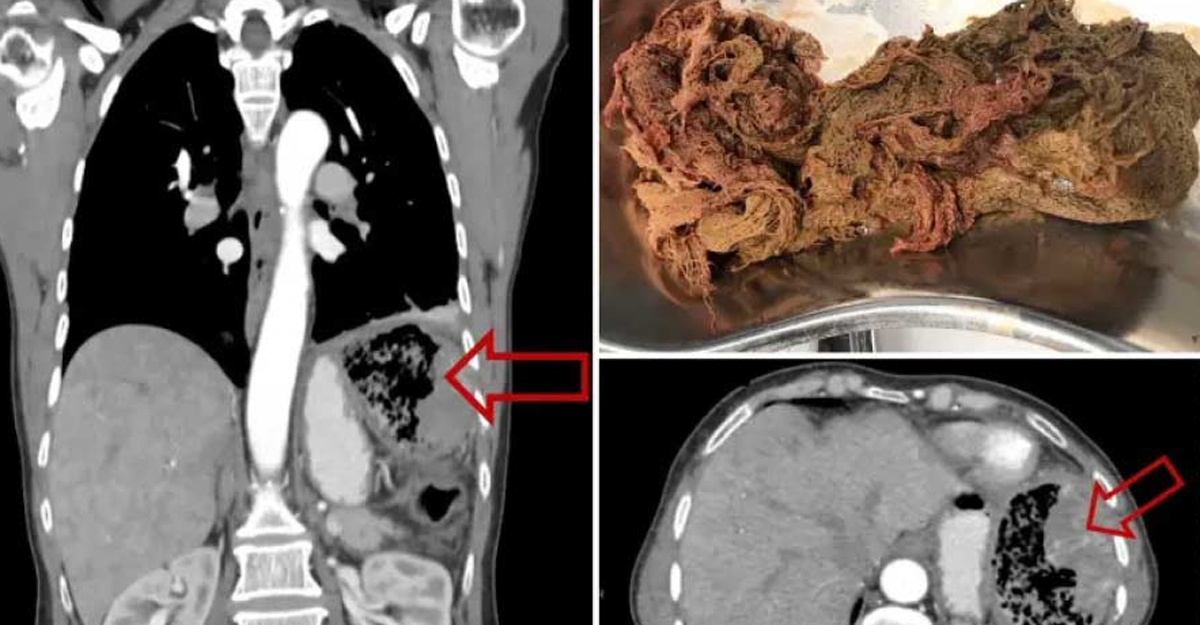

তীব্র পেটব্যথা নিয়ে হাসপাতালে ভর্তি হন এক নারী। পরীক্ষা নিরীক্ষা করে দেখা যায় পেটের ভেতরে আটকে রয়েছে গজ কাপড়। পরে অস্ত্রোপচার করে বের করা হয়।

চিকিৎসকদের ধারণা, প্রায় দুই দশক আগে হওয়া অন্য কোনো অস্ত্রোপচারের সময়ে সেই কাপড় ওই নারীর পেটের ভেতরে রয়ে গিয়েছিল।

চিকিৎসাশাস্ত্র সংক্রান্ত একটি জার্নালে প্রকাশিত প্রতিবেদন থেকে জানা গেছে, ১৯৯৯ সালে ‘গ্যাস্ট্রিক মিউকোসাল অ্যাডিনোকার্সিনোমা’ নামক ক্যানসারে আক্রান্ত হন ওই নারী। ফলে তার করতে হয় একাধিক অস্ত্রোপচার। চিকিৎসার পর তাকে ক্যানসারমুক্ত ঘোষণা করেন চিকিৎসকরা। এরপর প্রায় দুই দশক তেমন কোনো সমস্যা ছিল না তার। কিন্তু কিছু দিন আগে পেটের এক পাশে প্রবল যন্ত্রণা শুরু হয় তার। ফুলে ওঠে ডান পা। তারপরই হাসপাতালে নিয়ে যাওয়া হয় তাকে।

হাসপাতালে আলট্রাসনোগ্রাফি করা হয় ৬৫ বছর বয়সী ওই নারীর। তাতেও প্রথমে বোঝা যায়নি পেটের ভেতরে থাকা জিনিসটি কী। পরে অস্ত্রোপচারের পর বোঝা যায়, ভেতরে আটকে ছিল গজ কাপড়!

তবে কোনো উপসর্গ ছাড়াই এত দিন কীভাবে এই কাপড় রোগীর পেটের ভেতরে রইল, তা ভেবে অবাক চিকিৎসকরা।